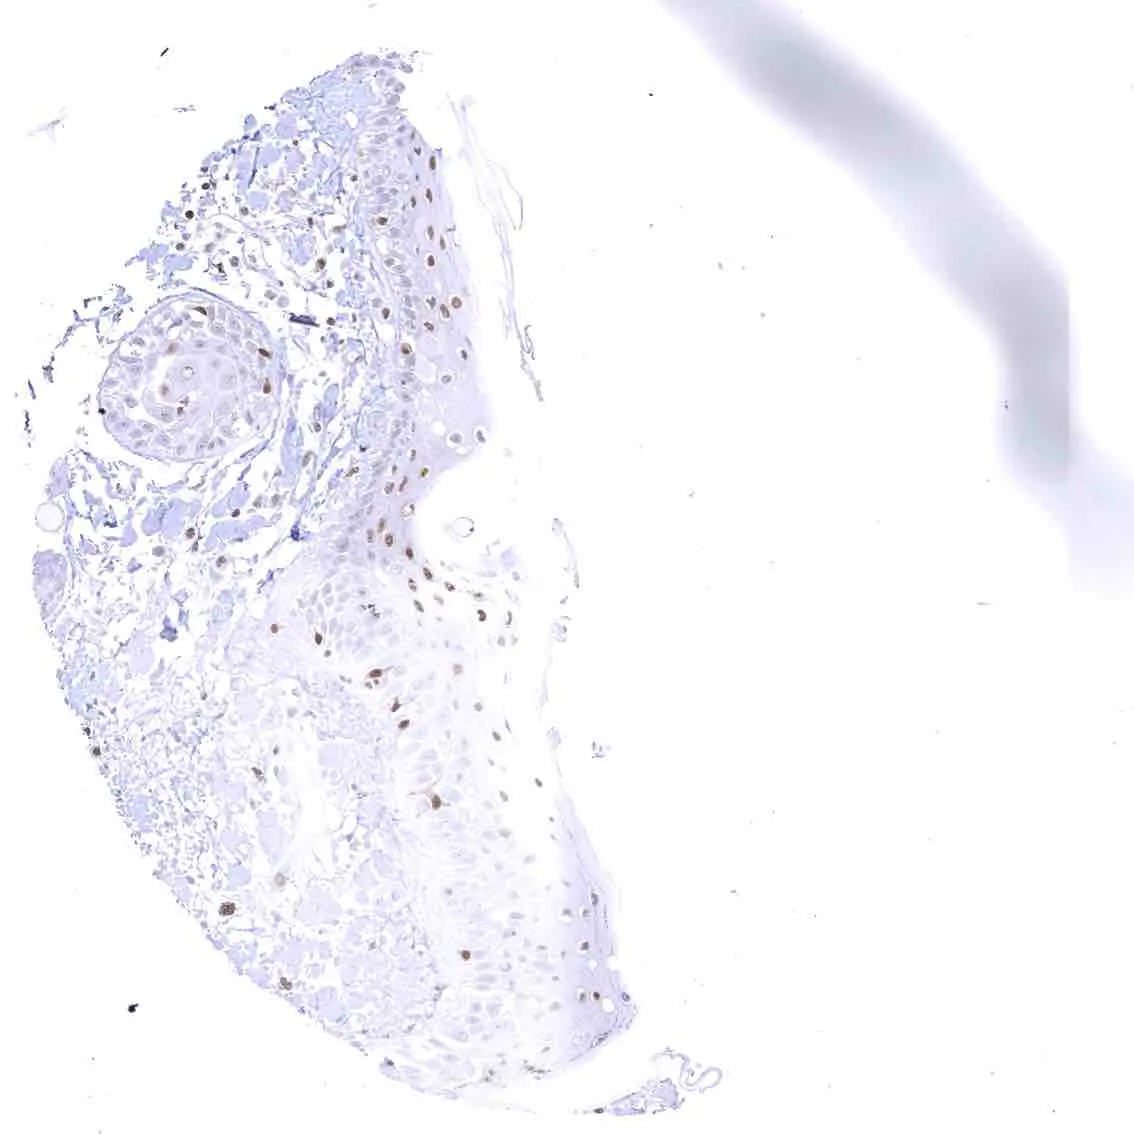

Uterus, ectocervix – Nuclear staining of squamous epithelial cells predominates in the more mature cell layers (top 50_ of the epidermis).